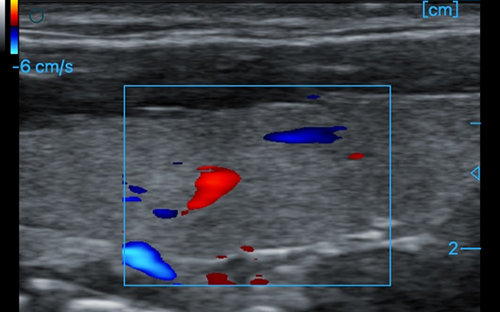

Thyroid + CF

Thyroid + CF